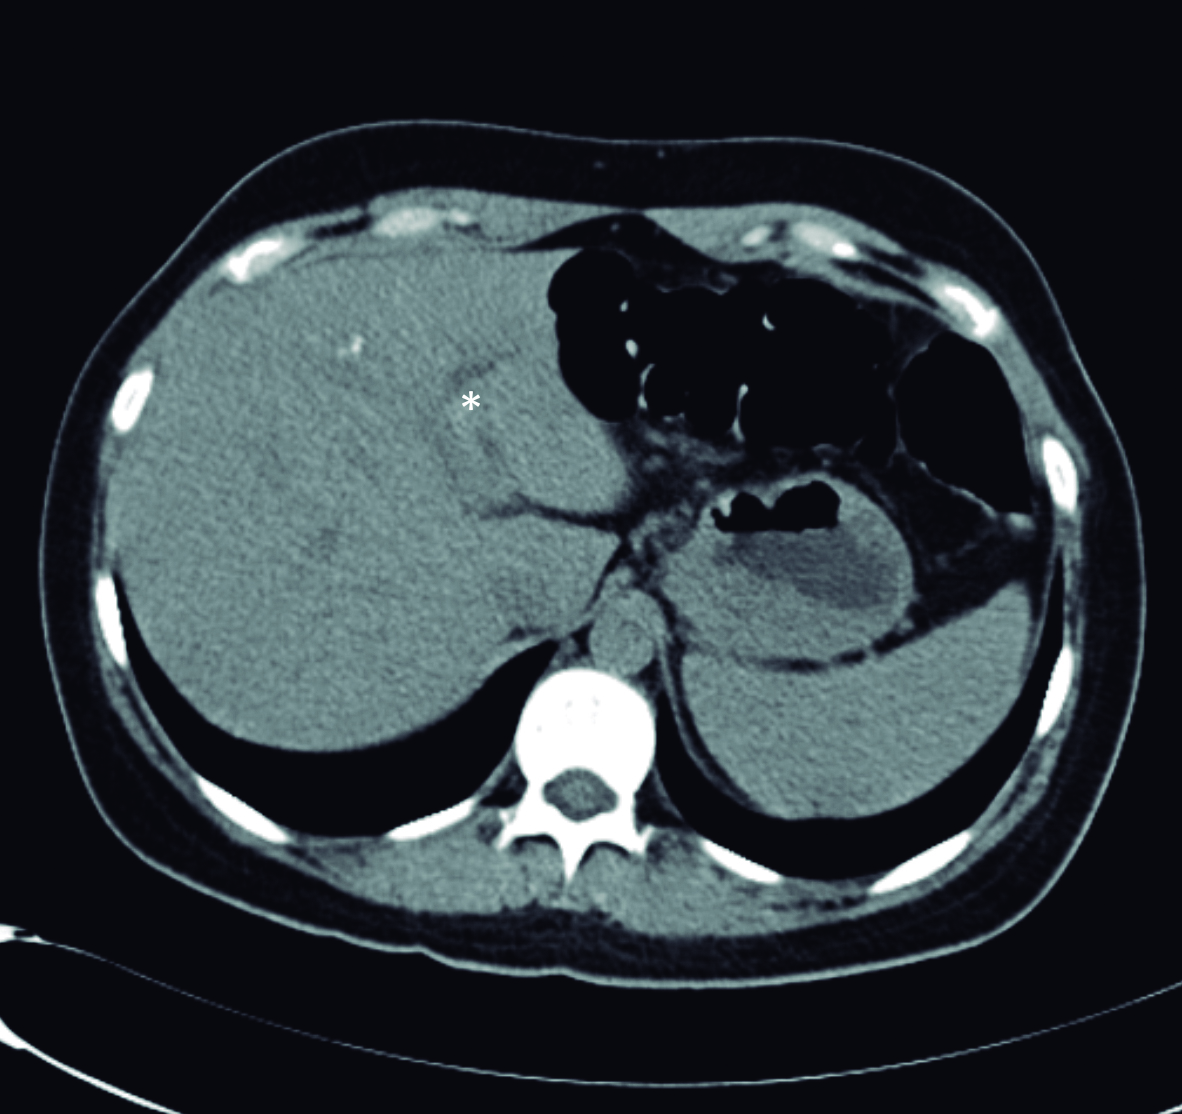

Con estos hallazgos, el equipo tratante solicita tomografía computarizada para completar valoración. La misma se realizó sin medio de contraste, dado dificultades en la punción de la paciente. Se observa imagen lineal hiperdensa dentro de la luz del colédoco, el cual se encuentra dilatado con un diámetro máximo 12mm (Fig. 2)

Figura 2. Tomografía computarizada plano axial sin medio de contraste

a y b) Se observa imagen lineal hiperdensa que corresponde

al Ascaris dentro de la luz de la rama izquierda del conducto

hepático y dentro del conducto hepático común (*).

La tomografía computarizada no es el método de elección para el diagnóstico de la ascaridiasis en la vía biliar y si la ecografía demuestra la imagen típica debería evitarse su uso o indicarse una resonancia magnética si hay dudas de los hallazgos. (13) De todas formas, la tomografía permite en algunos casos identificar los parásitos dentro de la vía biliar y valorar posibles complicaciones. La identificación de los parásitos es más sencilla en la tomografía sin contraste, en la que aparecen como estructuras tubulares hiperdensas rodeadas de bilis hipodensa. En los cortes axiales, al igual que en la ecografía, se visualiza la típica imagen en diana dada por el parásito dentro de la vía biliar dilatada. (14)